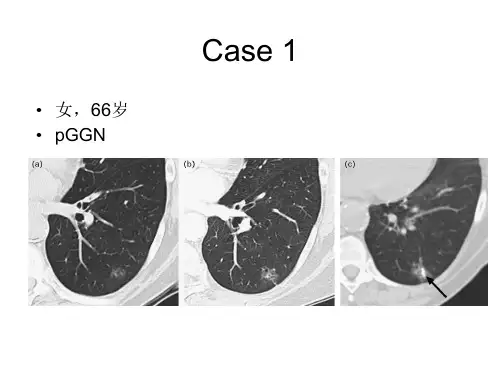

2、病灶大小、部位、形态

BAC或含BAC的混合腺癌好发于胸膜下。 肺癌多呈类圆形典型肿块(长、宽、高大致 相等);炎性病变多呈三角形、长条形及片 状或长宽高不等的不典型肿块,尽量冠状位 及矢状位重建。